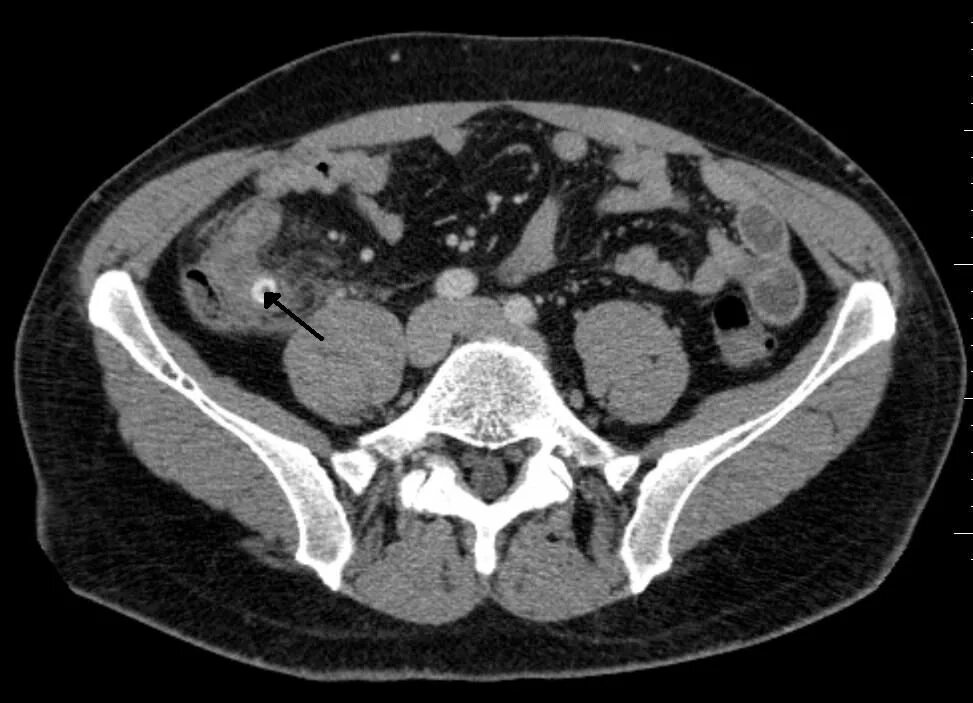

Малом тазу аппендицит